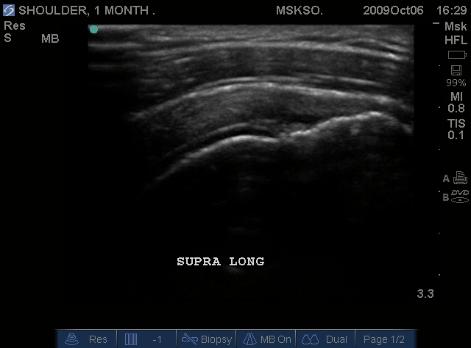

Long axis Supraspinatus tendon over lateral Greater Tuberosity. (lateral greater tuberosity is flat relative to the anterior) Tendon retraction is seen over cartilage interface sign of the humeral head.

Slightly anterior movement of the probe to visualize the full detail of the tear only for this case study purpose.